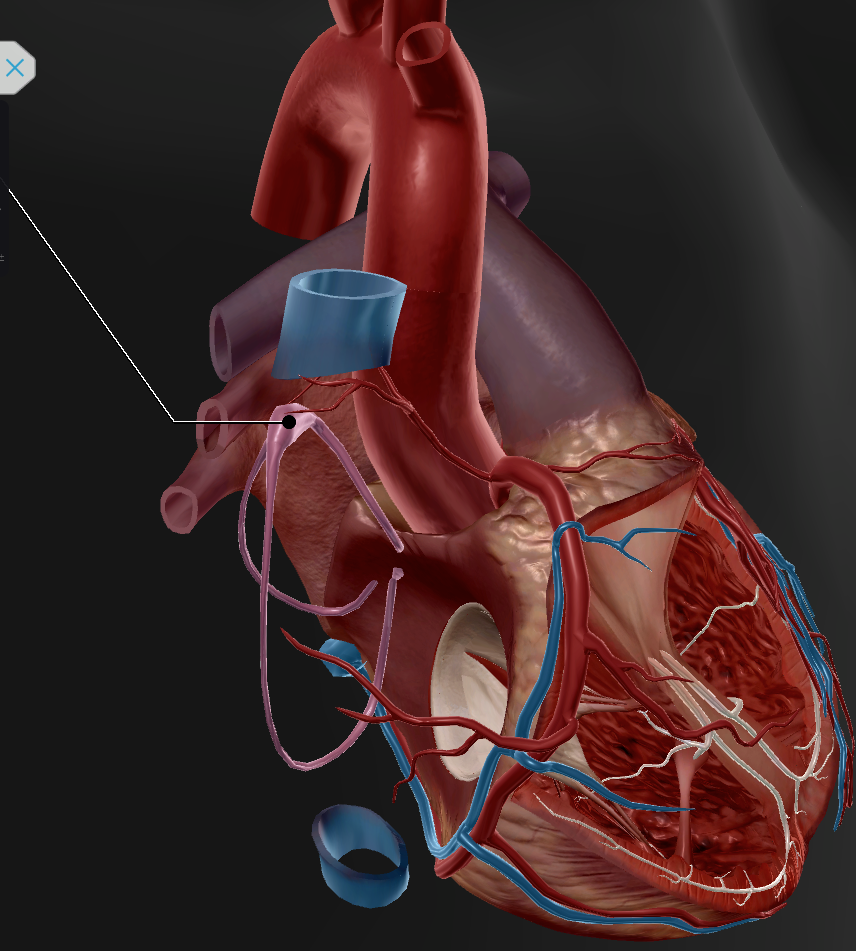

Anterior Interventricular Artery

Circumflex Branch

Coronary Artery

Middle Cardiac Vein

AV Node

SA Node

Bundle of His

Coronary Sinus

Anterior Interventricular Sulcus

Coronary Sulcus

Small Cardiac Vein

Anterior Cardiac Vein

Coronary Veins

Marginal Branch

Circumflex Artery

Great Cardiac Vein